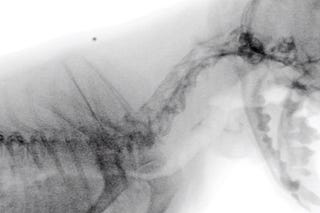

Empleo de fluoroscopia en colapso traqueal

Ejemplo gráfico de esta herramienta diagnóstica.

Fluoroscopia en perros con colapso traqueal

Repasamos esta modalidad diagnóstica en perros con colapso traqueal.